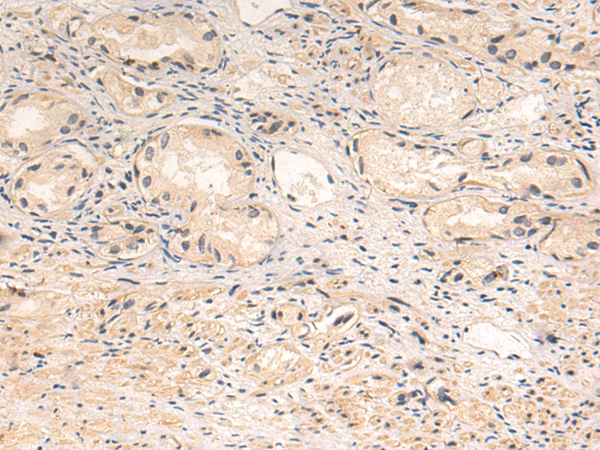

分类: 科研抗体货号: P10608别名: MCPH19; beta'-COP应用: IHC反应种属: Human, Mouse, Rat